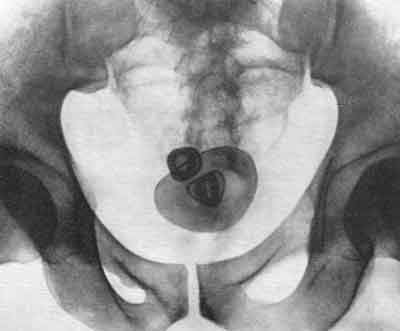

Диагностика

При камнях в мочевом пузыре симптомы могу выявляться в разной степени, однако, в любом случае, они являются основанием для визита к врачу. В ходе диагностики данное предположение будет подтверждено или опровергнуто. Необходимые исследования позволят определить не только наличие камня, но и его точное расположение, размер, характер камнеобразующего вещества, а также наличие/отсутствие сопутствующих заболеваний и т.д.

Как правило, в этом случае проводятся:

- общий анализ мочи;

- общий анализ крови;

- анализ мочи на камнеобразующую функцию;

- рентгенографическое исследование;

- УЗИ и др.

Если появятся основания предполагать наличие прочих заболеваний, могут быть назначены дополнительные исследования и меры диагностики, какие именно, в каждом отдельном случае определяет лечащий врач. После получения исчерпывающей информации касательно данной болезни, пациенту назначается адекватное лечение, в частности определяется, каким именно способом предстоит удалить камень.